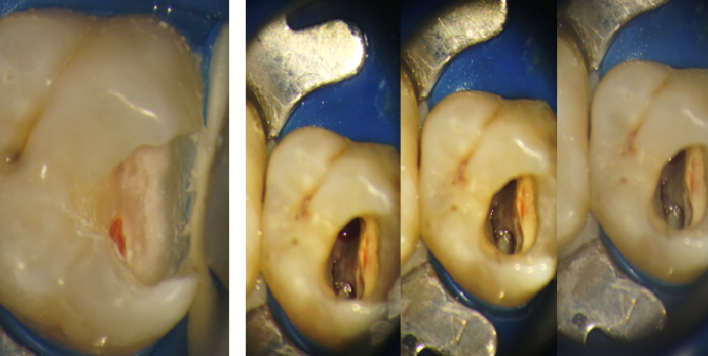

Într-adevăr, realizarea tratamentului de canal presupune, pe lângă îndepărtarea nervului, și sacrificarea unei părți din dinte, însă faptul că aceste tratamente se realizează la microscop, ne dă posibilitatea să fim extrem de conservativi cu dinții. Restaurarea adecvată a coroanei dentare după un tratament de canal scade substanțial posibilitatea de apariție a complicațiilor. Exemplu avem în acest caz de proces carios cu afectare pulpară, unde s-a îndepărtat, minim invaziv, doar țesutul afectat și s-a refăcut corespunzător peretele dentar (Fig. 4.4.2). Mai apoi a urmat tratamentul de canal. (Fig. 4.4.3)